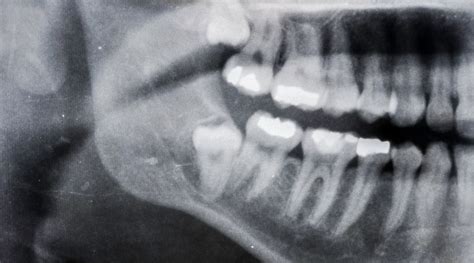

Después, para confirmar dicho diagnóstico, se recurre a las radiografías ya que permiten al dentista ver la posición exacta del diente dentro del hueso y determinar si está impactado.

El diagnóstico de los dientes retenidos se inicia con un examen clínico, en tu visita al dentista este evaluará tus síntomas y mirará la posición de tus dientes. El diagnóstico precoz es clave para determinar la causa y planificar un tratamiento adecuado.